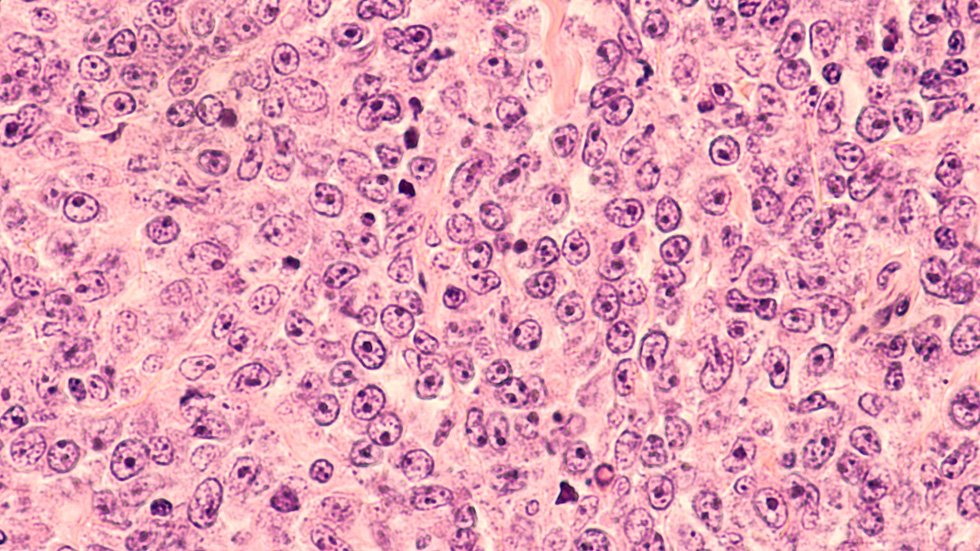

A study led by researchers from Mayo Clinic Comprehensive Cancer Center has found that the addition of brentuximab vedotin to standard chemotherapy treatment improves overall survival in patients with Hodgkin Lymphoma, when compared to the current standard of chemotherapy alone. Results of the research were presented by Stephen Ansell, M.D., Ph.D., at the 2022 American Society of Clinical Oncology Annual Meeting (ASCO) in Chicago and were published today in the New England Journal of Medicine.